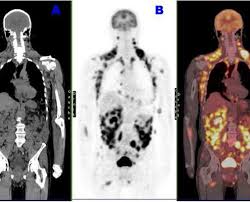

Scanner Thoracique Quelles Indications Fiches Sante Et Conseils Medicaux

Scanner Thoracique Quelles Indications Fiches Sante Et Conseils Medicaux from sante.lefigaro.fr

Infection Au Covid 19 Quelle Imagerie Le Generaliste

Infection Au Covid 19 Quelle Imagerie Le Generaliste from static5.legeneraliste.fr